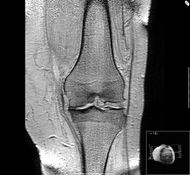

مرض خشونة المفاصل الانتكاسي Osteoarthritis أو degenerative joint disease يعتبر من أكثر الأمراض الروماتزمية شيوعا . يُسَبَّب المرض تأكل الغضروف المكون للمفصل (الغضروف هو المادّة المرنة القاسية التي تغطّي و تحمي نهايات العظام لتساعد في سهولة الحركة وتمنع تآكل العظام) تتآكل قطع الغضروف و تسبّب الألم و الورم في المفصل و هذا الألم و الورم يُسَمَّيَانِ التهاب المفصل الانتكاسي و مع تقدم الإنسان بالسن قد يتآكل جزء من الغضاريف مما يسبب احتكاك بين العظام المتقابلة وحدوث الالتهاب والألم.

يمكن أن يؤثّر المرض على أيّ مفصل في الجسم لكنة عادةً يؤثر على مفاصل الورك, الرّكبتين ، اليدين و العمود الفقريّ . عند حدوث المرض يبدأ الغضروف في التشقق وتحصل فتحات فيه و يمكن أن تنفصل قطع الغضروف في الفراغ المشترك للمفصل و تسبّب الألم عند ا لحركة . ليس لدى الغضروف نفسه خلايا عصبية ، و لذلك لا يشعر المريض بالألم بسبب تلف الغضروف نفسه ، و لكنّ يشعر بالألم بسبب العضلات, الأوتار, الأربطة و العظام المحيطة به .عد سنوات عديدة من تآكل الغضروف, قد يؤدي إلى احتكاك العظمة ضدّ العظمة المقابلة مما يزيد في الألم .

في بعض الأحيان قد يحتاج الطبيب إلي إ اختبارات معيّنة و التي تساعد في تأكيد التّشخيص و لتحديد مدى الضرر الموجود في المفصل, أو للتّمييز بين أنواع الرّوماتيزم المختلفة, قد تتضمّن هذه الاختبارات أشعة اكس, اختبارات الدّم أو اختبارات للسّائل ألزلالي الموجود في المفصل عند وجودة .